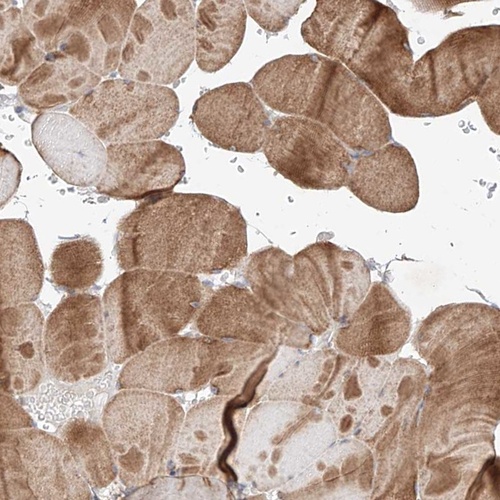

Immunohistochemical staining of human skeletal muscle shows moderate cytoplasmic positivity in myocytes.